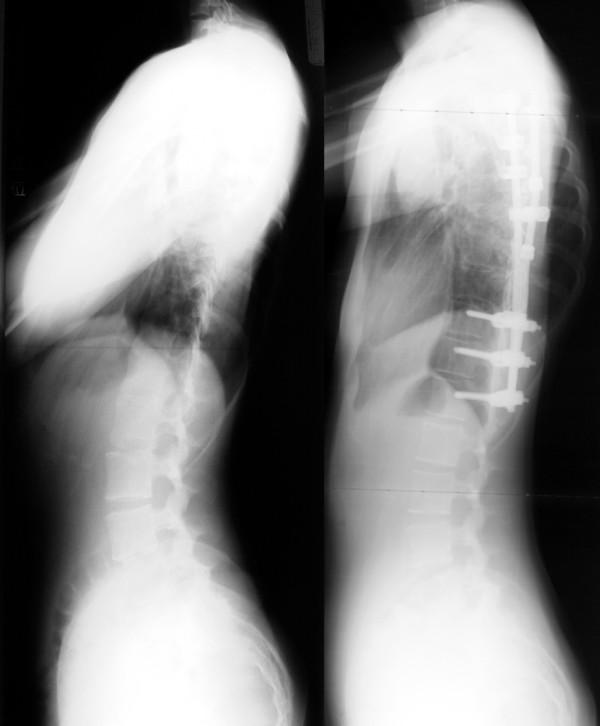

In this review, basic knowledge and recent innovation of surgical treatment for scoliosis will be described. Surgical treatment for scoliosis is indicated, in general, for the curve exceeding 45 or 50 degrees by the Cobb's method on the ground that:1) Curves larger than 50 degrees progress even after skeletal maturity.2) Curves of greater magnitude cause loss of pulmonary function, and much larger curves cause respiratory failure.3) Larger the curve progress, more difficult to treat with surgery.Posterior fusion with instrumentation has been a standard of the surgical treatment for scoliosis. In modern instrumentation systems, more anchors are used to connect the rod and the spine, resulting in better correction and less frequent implant failures. Segmental pedicle screw constructs or hybrid constructs using pedicle screws, hooks, and wires are the trend of today.Anterior instrumentation surgery had been a choice of treatment for the thoracolumbar and lumbar scoliosis because better correction can be obtained with shorter fusion levels. Recently, superiority of anterior surgery for the thoracolumbar and lumbar scoliosis has been lost. Initial enthusiasm for anterior instrumentation for the thoracic curve using video assisted thoracoscopic surgery technique has faded out.Various attempts are being made with use of fusionless surgery. To control growth, epiphysiodesis on the convex side of the deformity with or without instrumentation is a technique to provide gradual progressive correction and to arrest the deterioration of the curves. To avoid fusion for skeletally immature children with spinal cord injury or myelodysplasia, vertebral wedge ostetomies are performed for the treatment of progressive paralytic scoliosis. For right thoracic curve with idiopathic scoliosis, multiple vertebral wedge osteotomies without fusion are performed. To provide correction and maintain it during the growing years while allowing spinal growth for early onset scoliosis, technique of instrumentation without fusion or with limited fusion using dual rod instrumentation has been developed. To increase the volume of the thorax in thoracic insufficiency syndrome associated with fused ribs and congenital scoliosis, vertical expandable prosthetic titanium ribs has been developed.

在本综述中,将描述脊柱侧弯手术治疗的基础知识和最新创新。一般而言,脊柱侧弯的手术治疗适用于Cobb法测量角度超过45或50度的侧弯,原因如下:1)大于50度的侧弯即使在骨骼成熟后仍会进展。2)较大度数的侧弯会导致肺功能丧失,度数更大的侧弯会导致呼吸衰竭。3)侧弯进展越大,手术治疗越困难。后路融合内固定一直是脊柱侧弯手术治疗的标准方法。在现代内固定系统中,更多的锚钉用于连接棒与脊柱,从而实现更好的矫正效果,且植入物失败的频率更低。节段性椎弓根螺钉结构或使用椎弓根螺钉、钩和钢丝的混合结构是当今的发展趋势。前路内固定手术曾是胸腰段和腰段脊柱侧弯的一种治疗选择,因为它能在较短的融合节段下获得更好的矫正效果。最近,前路手术治疗胸腰段和腰段脊柱侧弯的优势已不复存在。最初对使用电视辅助胸腔镜手术技术进行胸椎侧弯前路内固定的热情已经消退。人们正在尝试各种非融合手术。为了控制生长,在畸形凸侧进行骨骺阻滞术(有无内固定)是一种提供渐进性矫正并阻止侧弯恶化的技术。对于脊髓损伤或脊髓发育不良的骨骼未成熟儿童,为避免融合,可进行椎体楔形截骨术来治疗进行性麻痹性脊柱侧弯。对于特发性脊柱侧弯的右胸弯,可进行多节段无融合椎体楔形截骨术。为了在生长期间提供矫正并维持矫正效果,同时允许早发性脊柱侧弯的脊柱生长,已开发出无融合或有限融合的双棒内固定技术。为了增加与融合肋骨和先天性脊柱侧弯相关的胸廓不全综合征患者的胸廓容积,已开发出垂直可扩张人工钛肋骨。